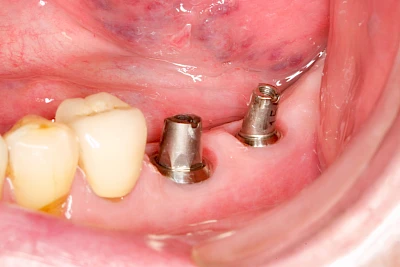

Implantate sind künstliche Zahnwurzeln. Nach einer gewissen Einheilzeit im Knochen (meist 3-6 Monate) erfolgt über einen separaten Aufbau (Abutment) die Befestigung einer Krone bzw. Brücke oder Zahnprothese.

In seltenen Fällen sind Implantate samt Aufbau aus einem Stück gefertigt. Auch gibt es Situationen, die ein Früh- oder sogar eine Sofortbelastung erlauben – dann kann die Einheilzeit der Implantate in den Knochen verkürzt oder sogar gänzlich darauf verzichtet werden.